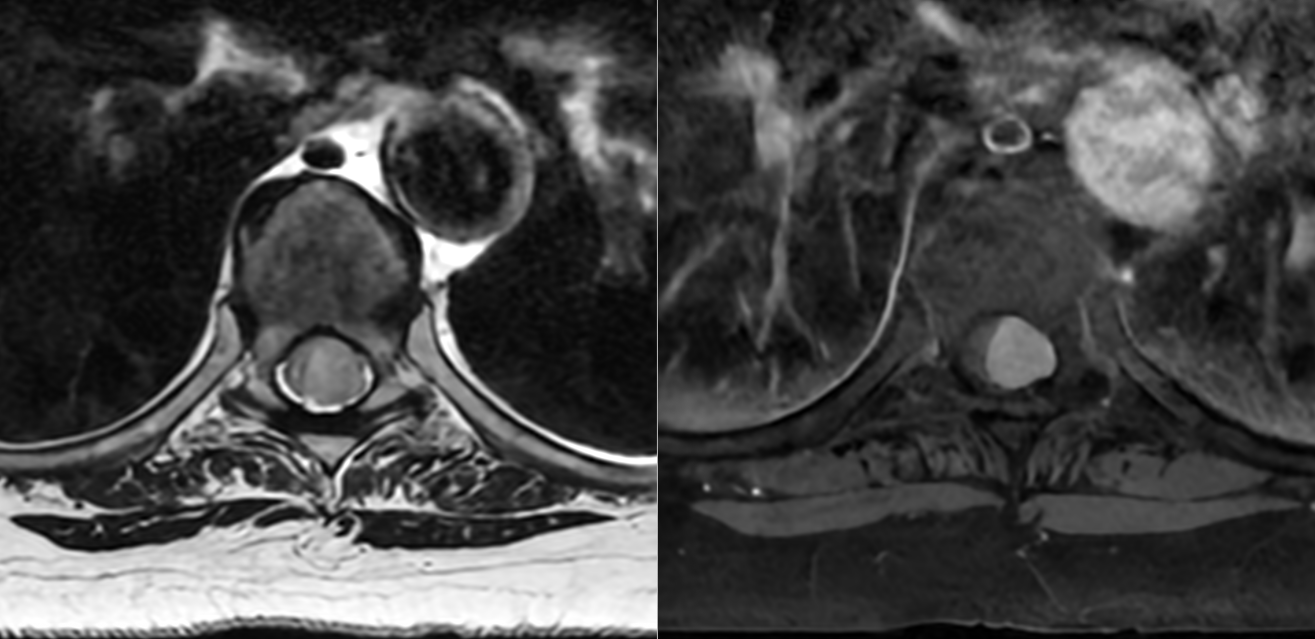

Meningiom spinal toracal – secțiuni sagitale

Meningiom spinal toracal – secțiuni axiale